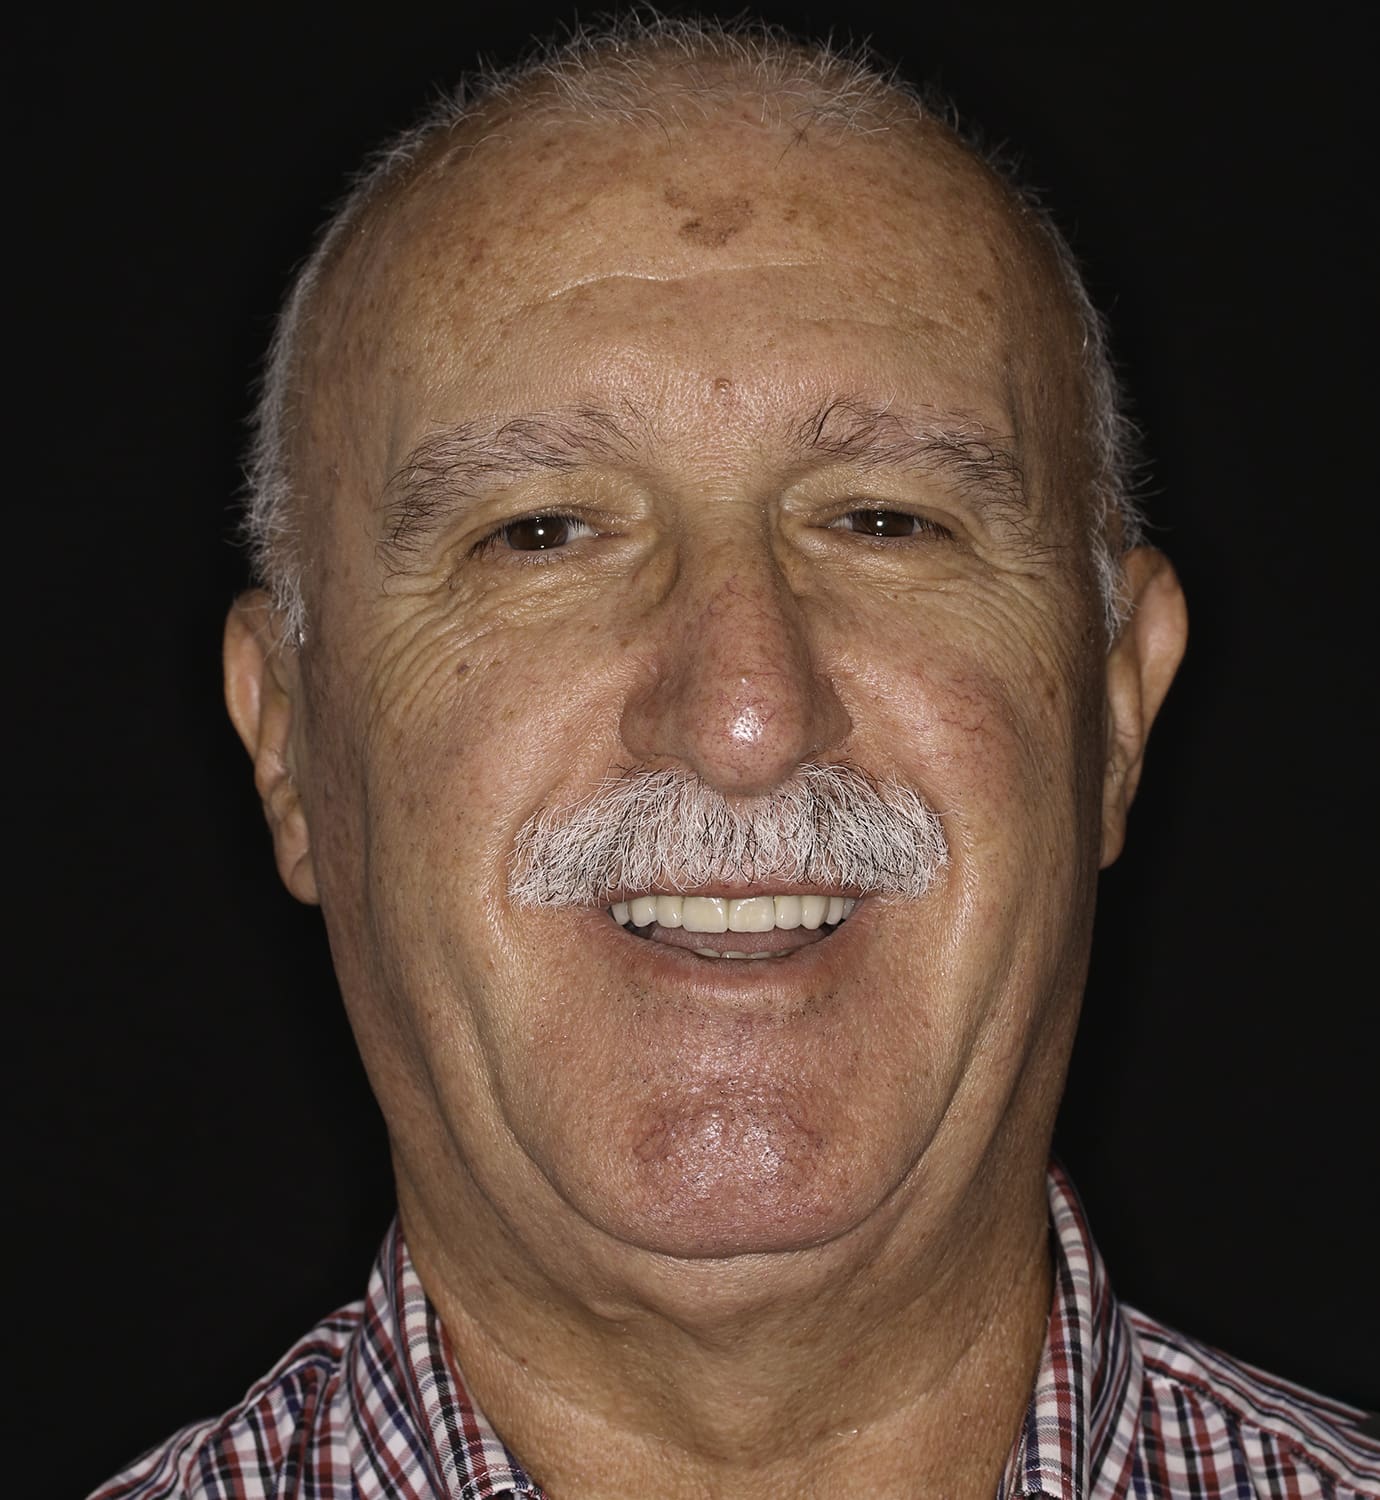

Analizando su caso, le propusimos una rehabilitación completa de la arcada superior con una prótesis híbrida sobre implantes. Con este plan de tratamiento queríamos alcanzar tres objetivos: mejorar su salud bucodental, facilitar el proceso de masticación y conseguir una oclusión perfecta y, por último, lograr un cambio significativo a nivel estético.

Jacinto aceptó el reto, animado por su mujer -también paciente de Ferrus & Bratos-. Ahora ya ha terminado el tratamiento, y dice notar grandes mejoras a la hora de comer y sentirse mucho más seguro de sí mismo con su nueva sonrisa.